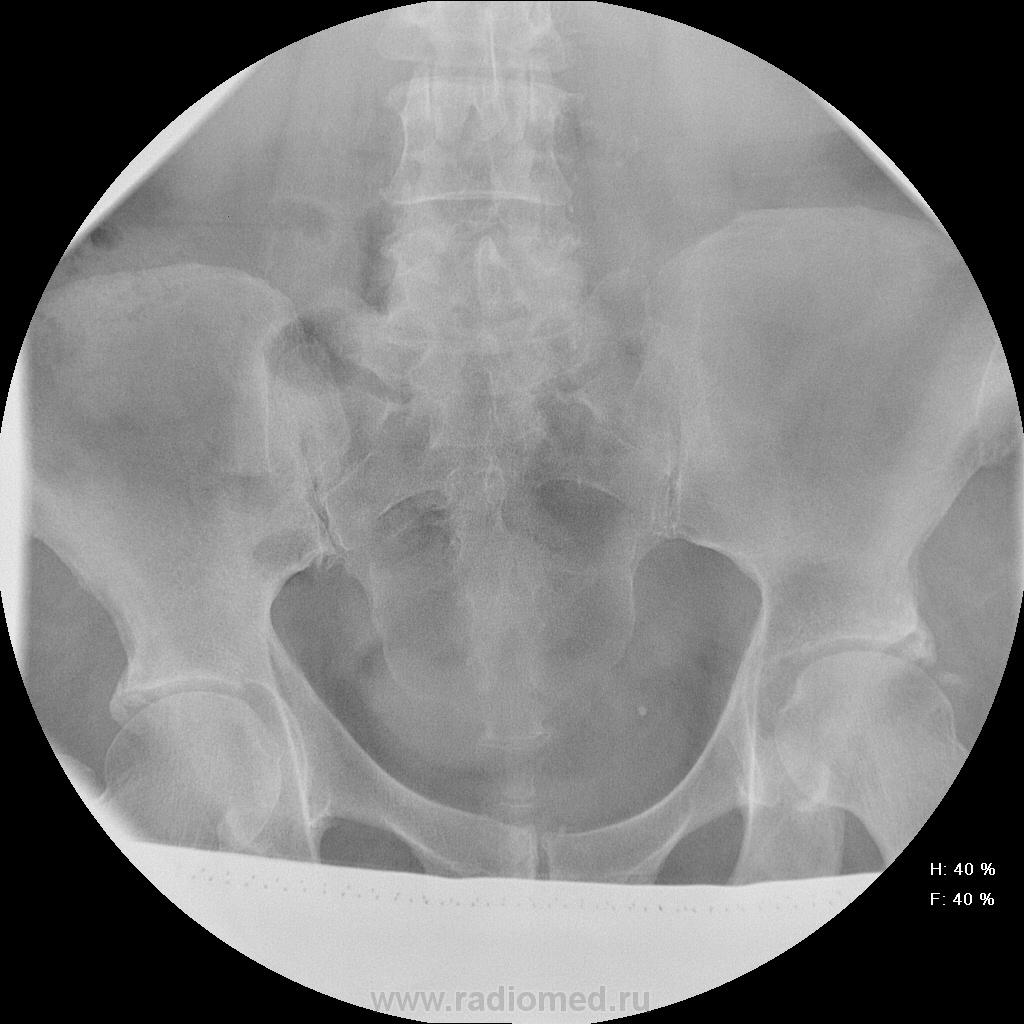

Женщина 55 лет, полная, поступила в неврологическое отделение с жалобами на боли в т.бедренных суставах,  области паха, больше слева. Лечили в поликлинике ДОА, остеохондроз- без эффекта, и направлили в стационар.

Остеохондроз от нижнегрудных позвоночно-двигательных сегментов и ниже, резко выраженный на уровне L5-S1 (3 степень снижения диска). Неполная люмбализация S1 - видны псевдосуставные щели на уровне боковых масс. Аномалия тропизма L5-S1: разноплоскостная ориентация щелей межпозвоночных суставов, один ближе к горизонтальной, второй - ближе к кософронтальной. Гиполордоз. Сколиоз. Деформирующий спондилез. Коксартроз 1 ст. с оссификацией крыш впадин. Флеболит(?!) в малом тазу слева, исключить конкремент в тазавой части левого мочеточника (ОАМ и т.д.; главное - экскреторная урография, желательно с прицельной РГ области мочевого пузыря в левой косой проекции на минуте 15-25).

Нисколько не оспаривая версию МКБ хочу обратить внимание на правосторонний сколиоз в вершиной в Л3-Л4 позв. сегменте, компенсаторные костные разрастания по правому контуру позвонков указанного сенгмента, нарушение статики позвонков - микролатеролистез Л3 вправо. Это может быть причиной весьма выраженной дорсопатии.

Ну раз мнений больше нет - Мы заподозрили деструкцию в области тела подвздошной кости над вертлужной впадиной слева и отправили на КТ (обратите внимание на разряжение костной структуры по сравнению с правой стороной). На КТ : множественные очаги деструкции позвонков , больше пострадал остистый отросток L4. Такие же очаги в тазовых костях, наиболее крупный как раз слева над вертлужной впадиной. Левая половина крестца почти полностью разрушена. Кроме этого, очаги в печени, надпочечниках. Тело матки увеличено, в области придатков слева - кистозное образование. После этого посмотрели на наши сникми - почти сразу все увидели, особенно пропажу остистого отростка L4.

Имеем мтс, нужно теперь найти первичный очаг...